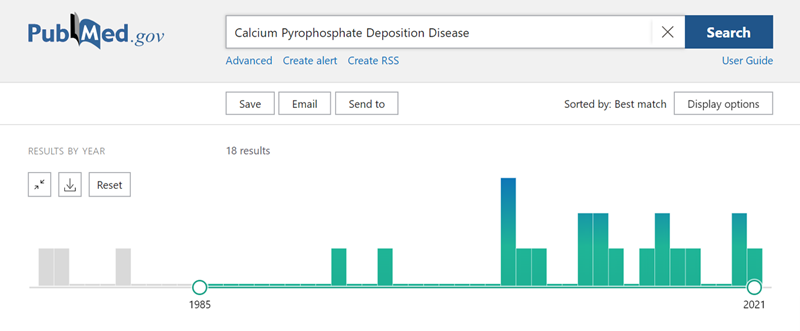

既往临床报道以Case reports居多